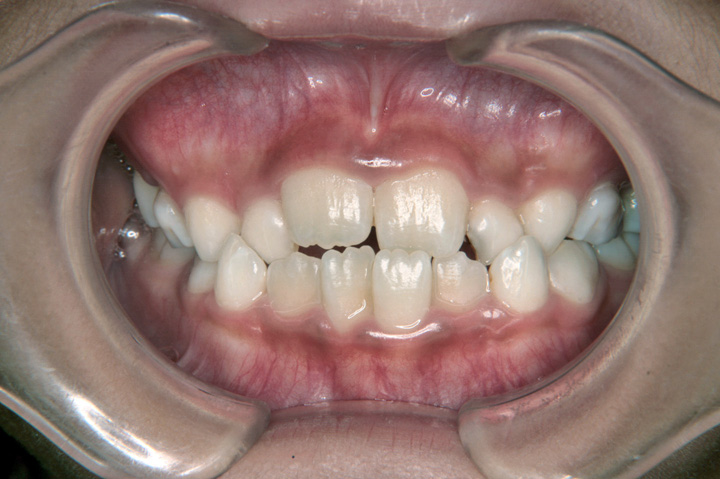

前歯の交叉咬合は、上顎の前歯の一部が、下顎の前歯のよりも内側に入っている状態です。かみ合わせが逆転することで、種々の不利益を引き起こします。通常は、叢生と複合することが多い不正咬合です。お子様の場合、低学年(7~9歳)であっても、交叉咬合と判断される場合は、受診をお勧めいたします。 その時期であれば、比較的良好な治療結果となることが多いと思います。成人の方の治療も可能ですが、負担のかかった歯肉などは、回復できない場合もあります。

症例(40)

【永久歯列 非抜歯】